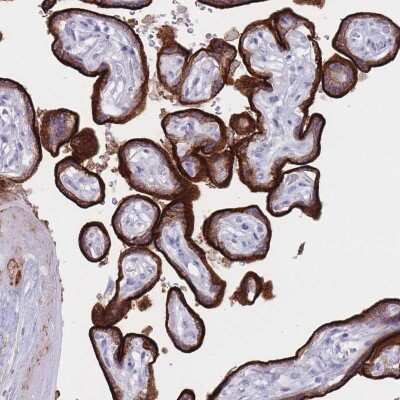

Immunohistochemistry: ST3GAL5 Antibody [NBP2-32612]

Immunohistochemistry: ST3GAL5 Antibody [NBP2-32612] - Staining of human placenta shows strong cytoplasmic positivity in trophoblastic cells.